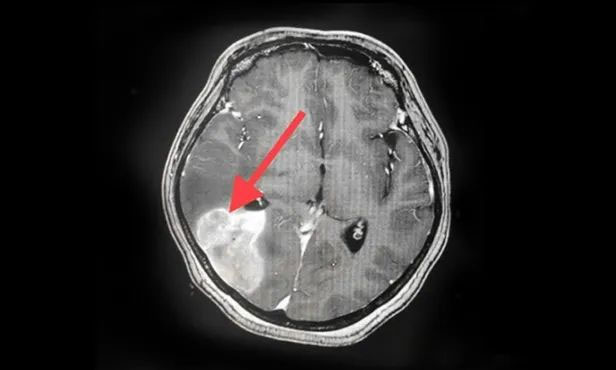

▲ 刚入院时病灶影像

▲ 完成穿刺,黑色囊液被顺利引流

▲ 经复查,病灶较前明显缩小

按照肿瘤复查的标准,复查影像显示王女士颅内病灶相较于来院时明显缩小。家属为此特意向陈琦主任致谢,并对医院的治疗和服务表达了充分肯定。